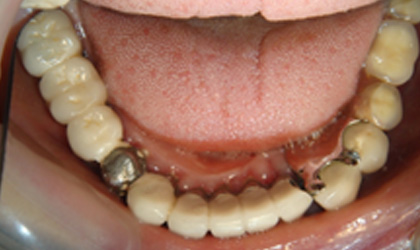

拆下牙橋前